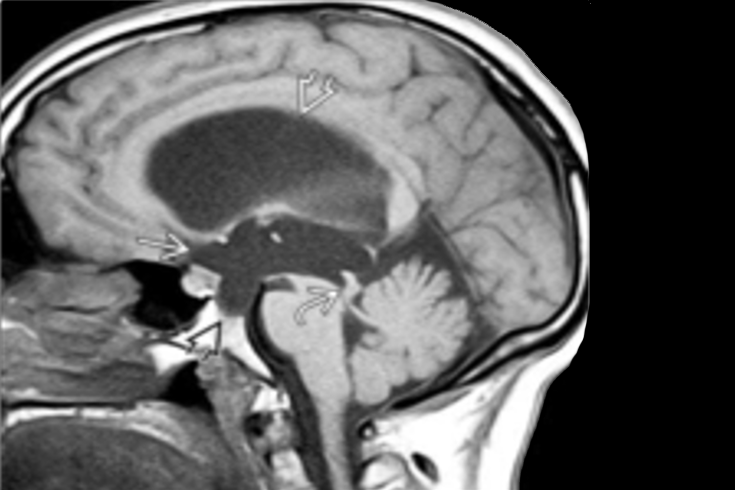

Hidrocefalia Obstructivă - stenoza de apeduct

Hidrocefalia obstructivă, cunoscută și sub denumirea de noncomunicantă, apare atunci când există un obstacol în circulația LCR-ului între cei patru ventriculi cerebrali: de exemplu:

- în cazul prezenței unor tumori cerebrale;

- în cazul stenozei de apeduct;

„Dacă în urma examenului IRM sau CT cerebral se evidențiază un sistem ventricular lărgit prin acumulare în exces de lichid cefalorahidian, fără a exista o cauză obstructivă, se confirmă suspiciunea de hidrocefalie. Suplimentar se poate efectua și o puncție lombară pentru a măsură presiunea lichidului, care trebuie să fie sub 24 cm H2O în cazul unei hidrocefalii cu presiune normală. În cazul unei presiuni de peste 24 cm H2O, ne gândim la o hidrocefalie obstructivă. Uneori, în urma acestei puncții, se evacuează o cantitate de aproximativ 30-40 ml LCR și, în funcție de evoluția clinică, adică dacă simptomatologia se ameliorează sau nu, se decide montarea unui sistem de drenaj”, precizează medicul neurochirurg.